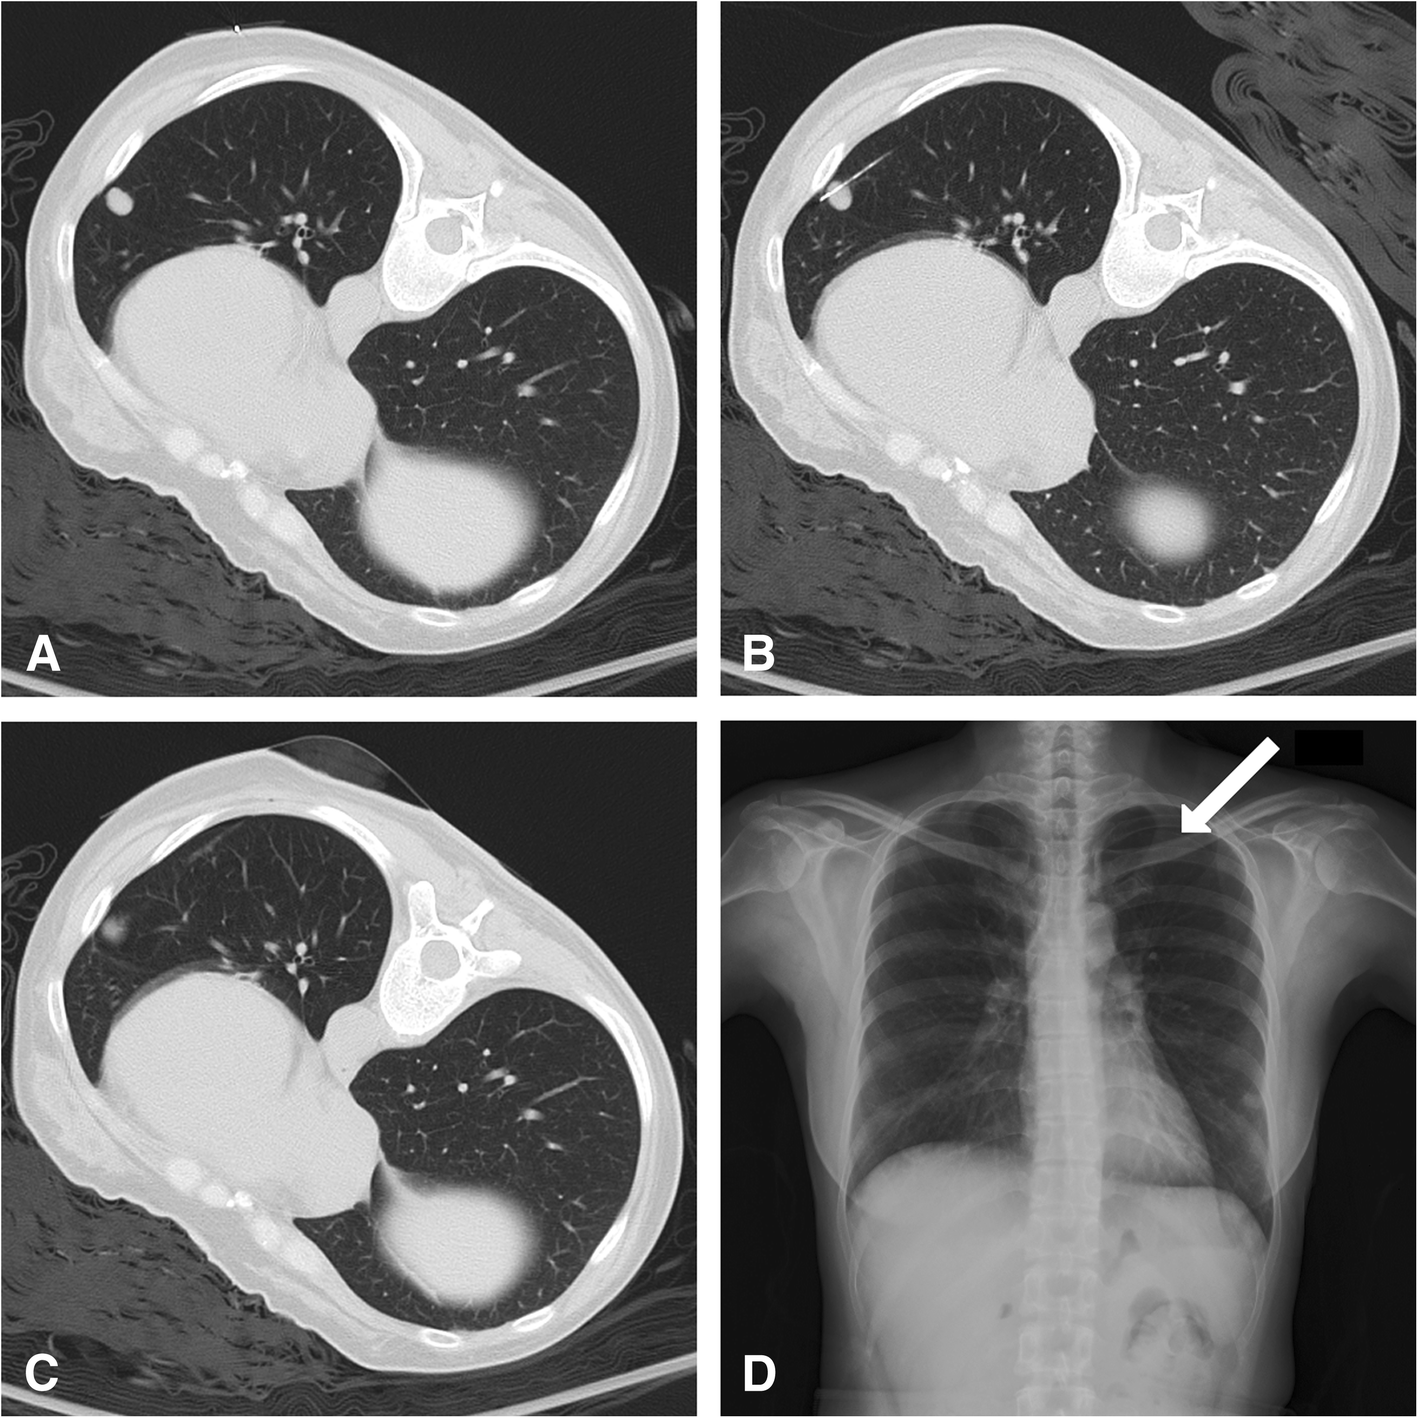

Fig. 1

CT-guided pulmonary biopsy in a 45-year-old female. a Pre-biopsy CT with standard lung window revealed a 10-mm nodule over the left lower lobe. A metallic marker was placed over the skin for location. b The biopsy was performed using a 17-gauge introducing needle and 18-gauge cutting needle. To prevent the needle from crossing the fissure and being blocked by the rib, a proper entry site was chosen. The final position of the cutting notch of the needle was just inside the nodule. c Post-biopsy CT revealed minimal pulmonary hemorrhage around the needle path, and no pneumothorax was found. d A standing chest X-ray was performed 24 hours after the procedure. The pleural line (arrow) over the left upper chest was visible, and pneumothorax over the left side was confirmed